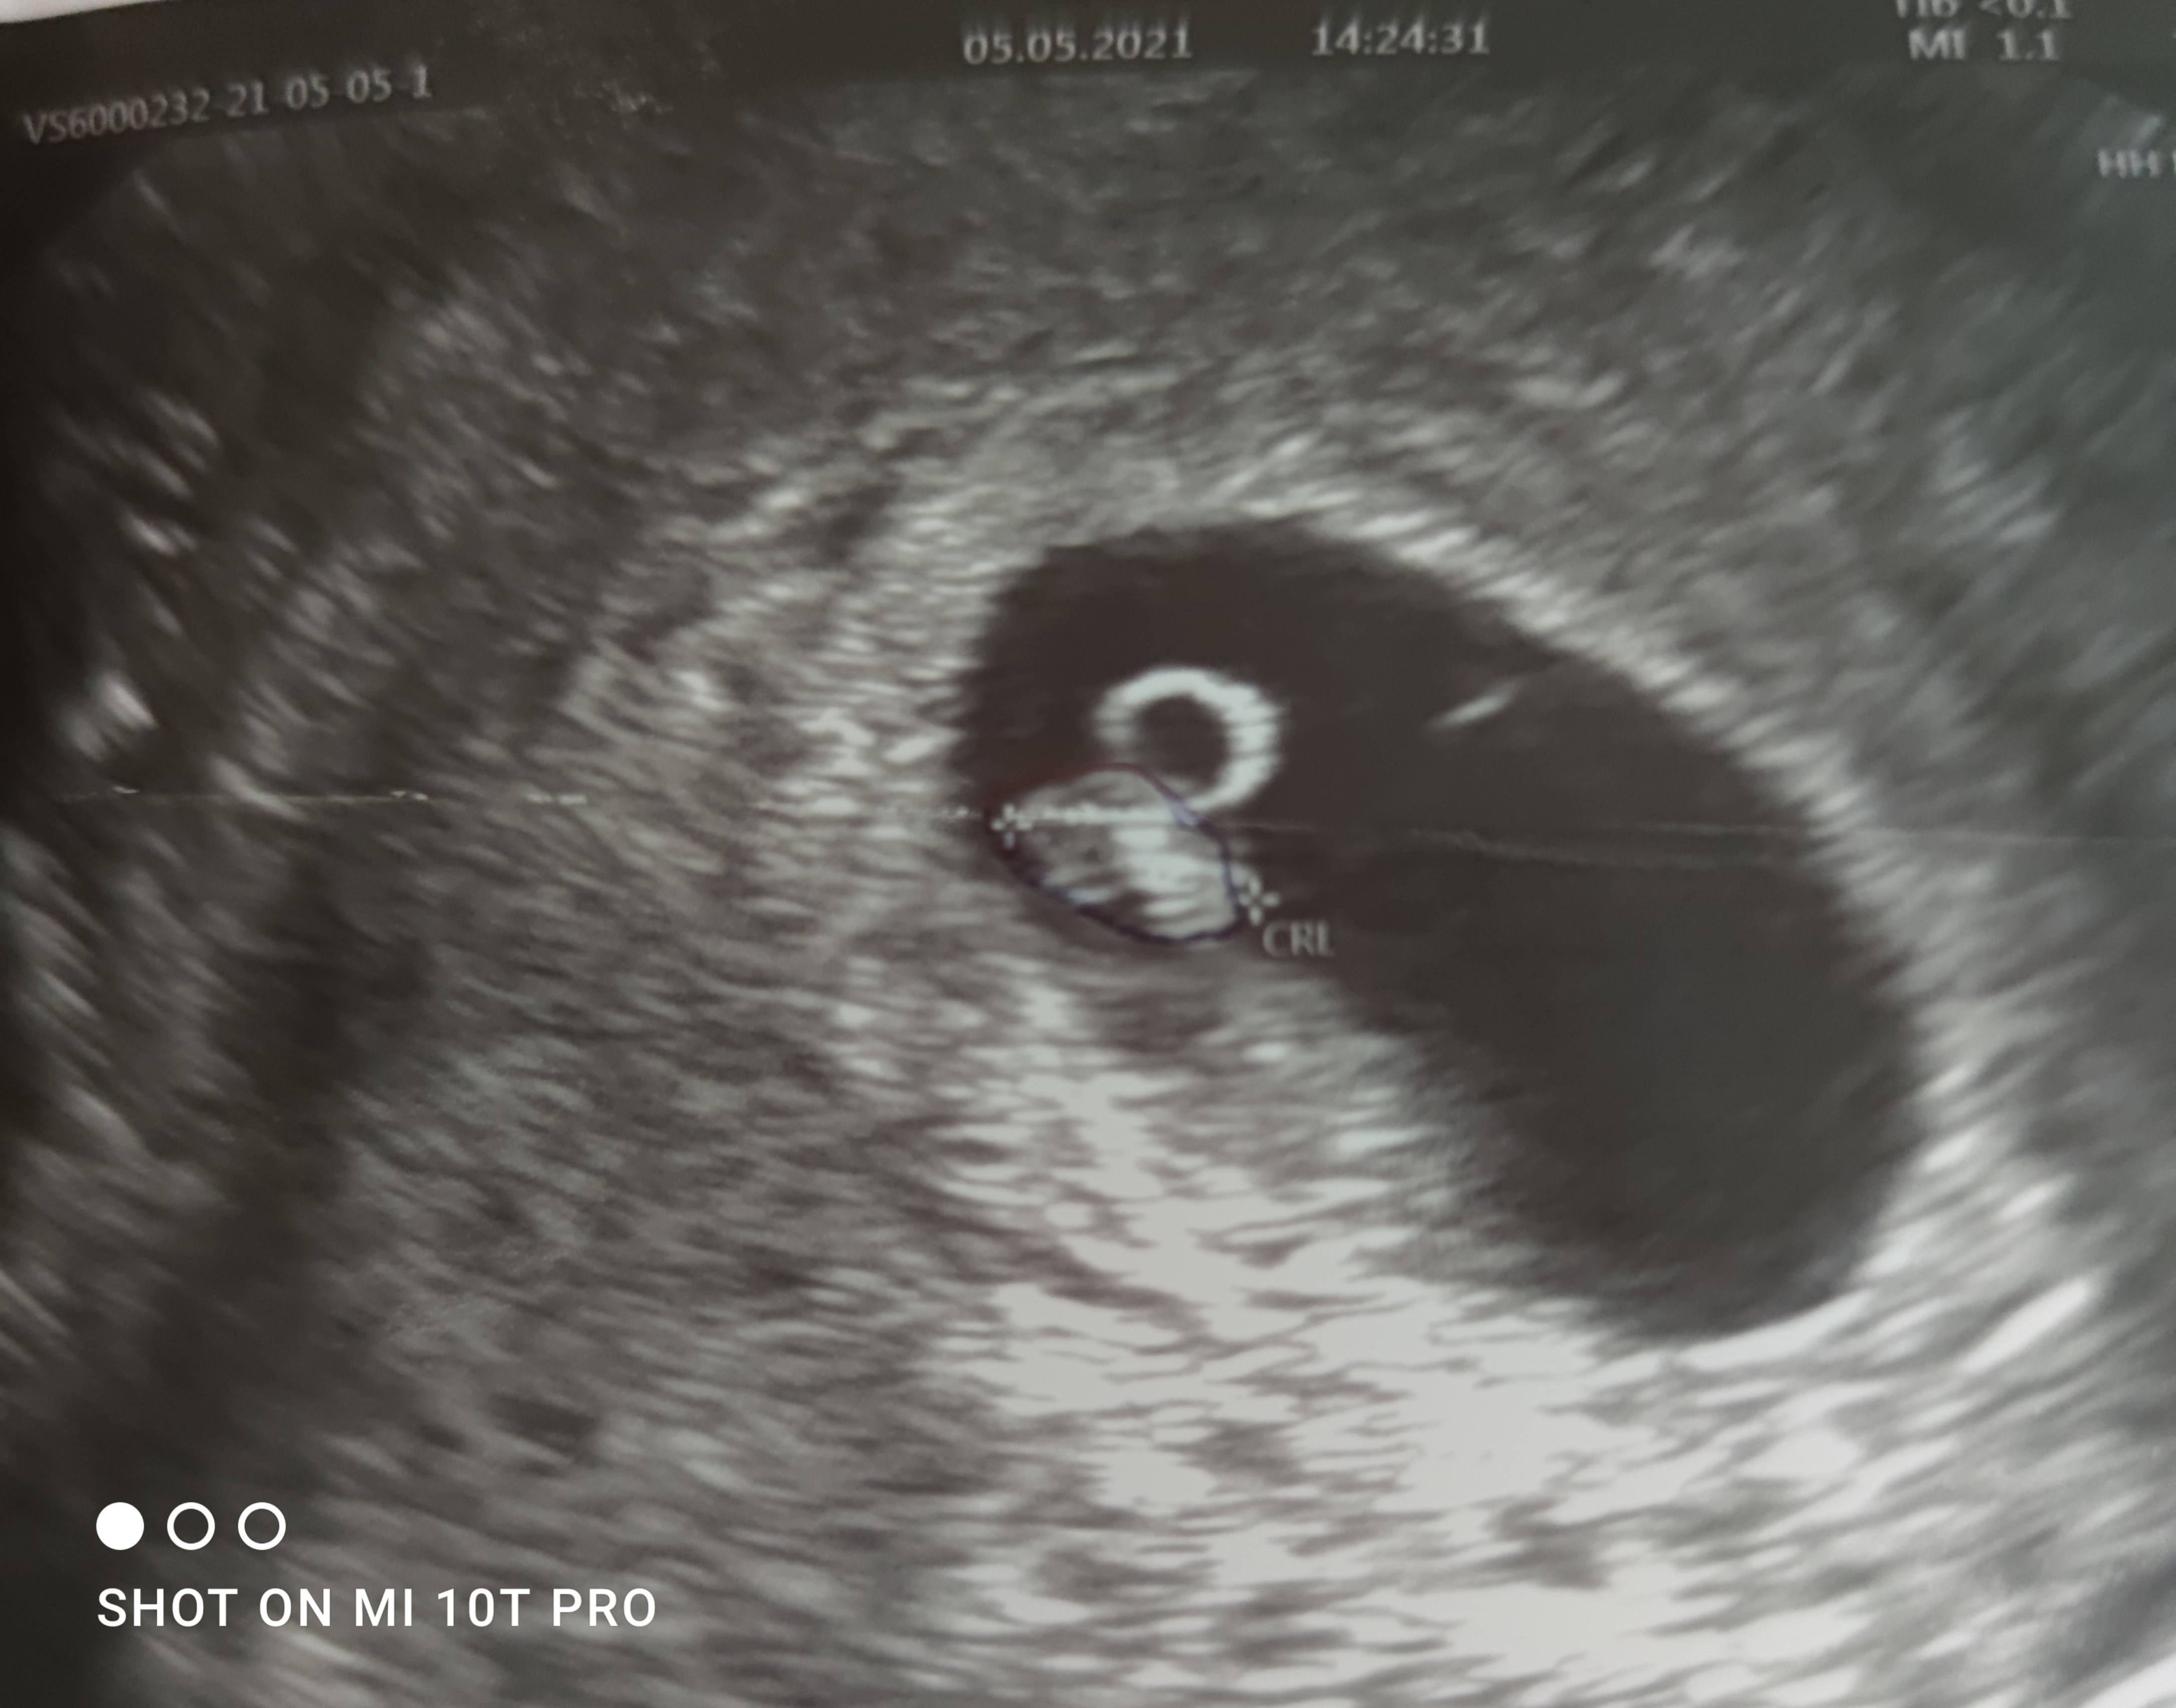

Dziewczyny ja też dziś zobaczyłam zarodek i serduszko ❤️ 6+3 ❤️ Wszystko jest w najlepszym porządku ❤️

IMG_20210505_155549.jpg